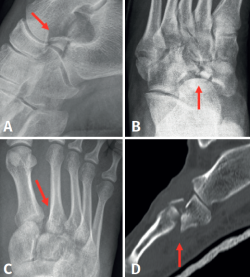

La edad media de la serie presentada es de 45 años (rango: 21-69 años). El seguimiento medio fue de 22 meses (rango: 12-65 meses). El mecanismo de acción de las fracturas fue, en 7 casos (53,8%), un traumatismo de alta energía tras accidente de tráfico, y, en los 6 casos restantes (46,2%), caída casual asociada a torsión de tobillo. Ninguna de estas fracturas se diagnosticó de forma aislada (Figura 2), objetivándose fractura de la pars anterior y cuerpo de calcáneo en 6 casos (46,2%), fractura de escafoides tarsiano en 4 casos (30,8%), en 2 casos (15,7%) lesión del complejo ligamentoso de Lisfranc y 1 caso (7,6%) de fractura-luxación de la base de los metatarsianos cuarto y quinto (Tabla 1).

Figura 2. Lesiones asociadas a fracturas de cascanueces de cuboides. A: fractura de la pars anterior del calcáneo; B: fractura de escafoides tarsiano; C: lesión de Lisfranc; D: fractura de la base de los metatarsianos cuarto y quinto.